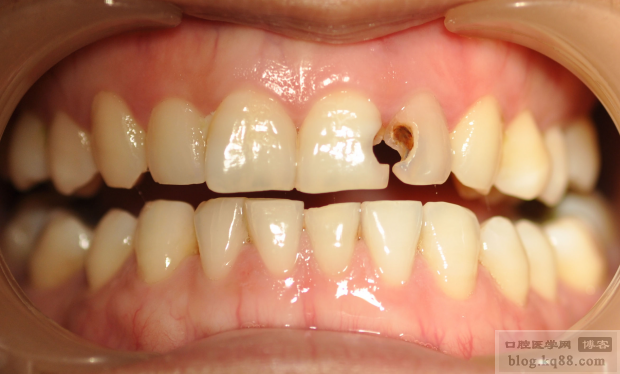

患者,女,28歲,前牙原充填材料脫落來診。

檢查:21遠中22近中充填物脫落,色暗,21牙冠變色

治療方案:1:21樹脂美容性修復(fù)

2:22一次性根管充填,建議冠套修復(fù)(患者考慮經(jīng)濟因素,強烈要求先充填)